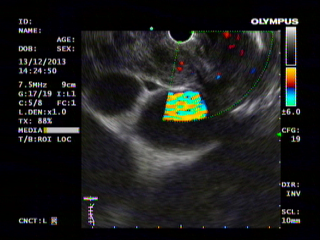

EUS is an ultrasound of internal structures surrounding the GI tract with the help of an endoscope. EUS provides excellent resolution of the pancreas, biliary system, and the mediastinum.

During EUS, the sample can be taken from the nodes in the mediastinum, tumor of pancreas and bile duct. With the help of endoscopic ultrasound, various collections can be drained internally in the stomach or rectum and the major surgeries can be avoided.